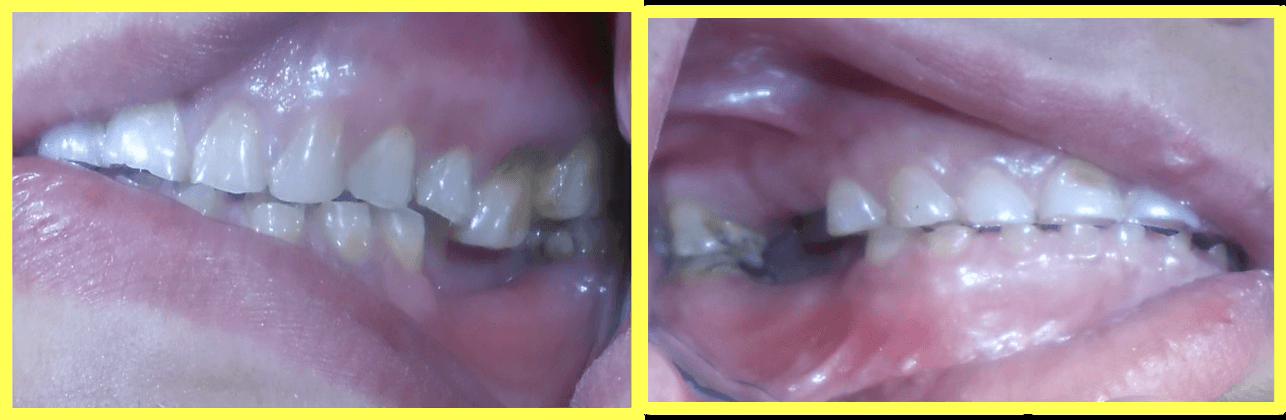

Root canal treatment performed on all remaining attrited teeth to ensure long-term viability before crown placement.

Temporary crowns were cemented to protect prepared teeth and maintain function during healing period.

Permanent Porcelain Fused to Metal (PFM) crowns were custom-fabricated and cemented. Implants were delayed loaded after 3 months of healing.

"After years of struggling with worn and missing teeth, I finally have a beautiful, functional smile. The entire team made the process smooth and comfortable. I can eat, smile, and laugh confidently again!"